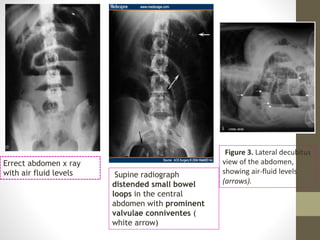

Errect abdomen x ray

with air fluid levels Supine radiograph

distended small bowel

loops in the central

abdomen with prominent

valvulae conniventes (

white arrow)

Figure 3. Lateral decubitus

view of the abdomen,

showing air-fluid levels

(arrows).